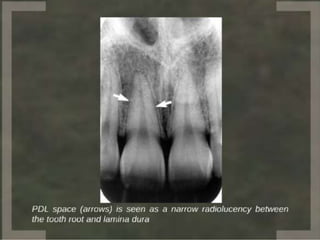

The periodontal

ligament

occupies the

periodontal

space. Between

the cementum

and periodontal

surface of

alveolar bone.

Width

ranges from

0.15 to 0.38

mm